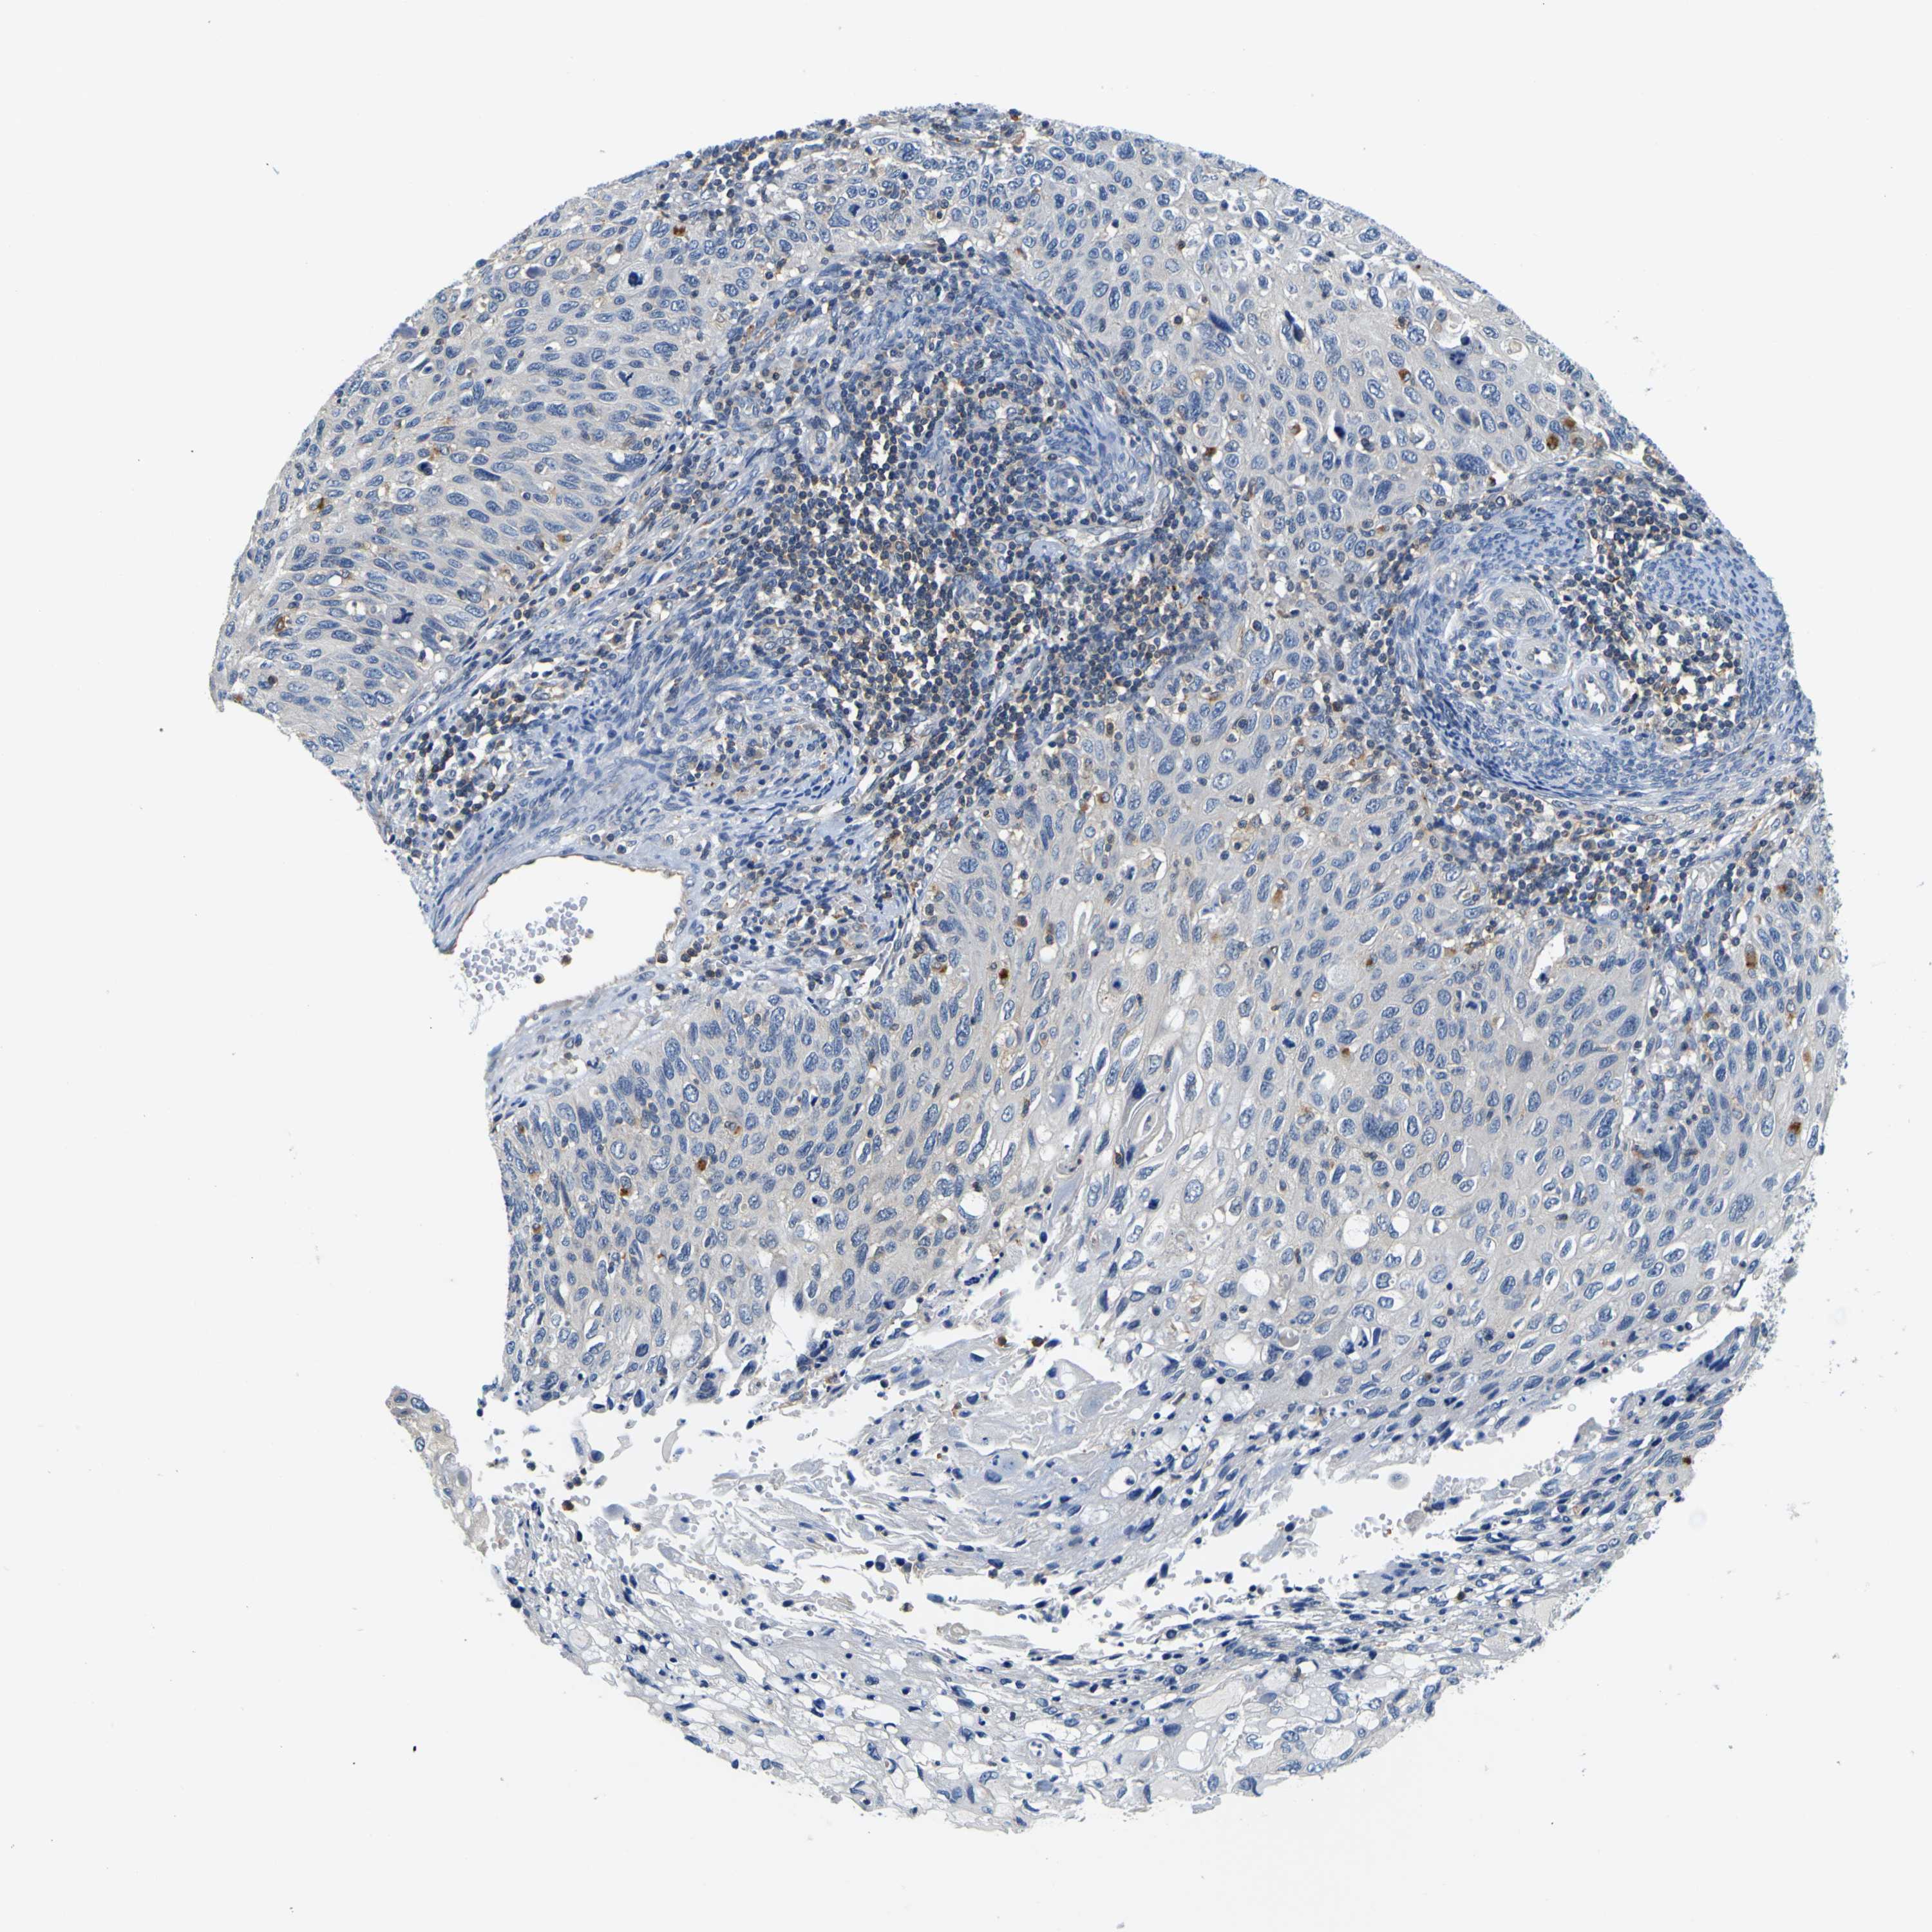

CERVICAL CANCER - Protein expressioni

A mouse-over function shows sample information and annotation data. Click on an image to view it in a full screen mode. Samples can be filtered based on level of antibody staining by selecting one or several of the following categories: high, medium, low and not detected. The assay and annotation is described here.

Note that samples used for immunohistochemistry by the Human Protein Atlas do not correspond to samples in the TCGA dataset.

Antibody stainingi

Antibody staining in the annotated cell types in the current human tissue is reported as not detected, low, medium, or high, based on conventional immunohistochemistry profiling in selected tissues. This score is based on the combination of the staining intensity and fraction of stained cells.

Each image is clickable and will lead to virtual microscopy that enables deeper exploration of all samples and also displays staining intensity scores, fraction scores and subcellular localization as well as patient and tissue information for each sample.

Antibody HPA012128

Antibody HPA012297

Staining

High

Medium

Low

Not detected

Intensity

Strong

Moderate

Weak

Negative

Quantity

>75%

75%-25%

<25%

None

Location

Nuclear

Cytoplasmic/membranous

Cytoplasmic/membranous,nuclear

Squamous cell carcinoma, NOS

Adenocarcinoma, NOS